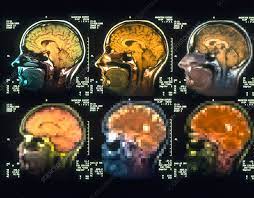

The brain, a three-pound mass of tissue, holds the key to what makes us uniquely human. It's a marvel of nature, responsible for our thoughts, emotions, memories, and actions. Yet, despite centuries of study, it remains one of the most enigmatic and least understood organs in the human body. In this blog post, we embark on a journey to explore the intricacies of the brain, uncovering its mysteries and marvels along the way. The Brain: An Astonishing Complexity

At first glance, the brain might appear as a homogeneous blob, but in reality, it's an exquisitely organized and highly specialized structure. Comprising billions of neurons and trillions of synapses, it forms a complex network that facilitates communication within the brain and throughout the body. This network gives rise to our thoughts, sensations, and behaviors, shaping every aspect of our existence.

One of the fundamental challenges in neuroscience is deciphering the neural code—the language of the brain. How do neurons encode and transmit information? What patterns of activity underlie our perceptions and actions? Scientists have made significant strides in this area, employing techniques ranging from electrophysiology to functional imaging. Through these methods, they've begun to unravel the intricacies of neural circuits and the neural computations that underlie our cognitive functions.